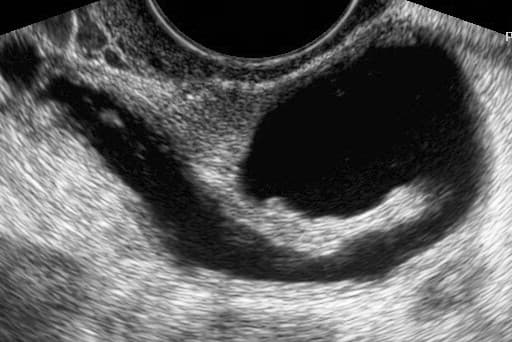

Fallopian tube obstruction, also known as fallopian tube occlusion is a major cause of female infertility. Blocked fallopian tubes are unable to let the ovum and the sperm converge, thus making fertilization impossible. Fallopian tubes are also known as oviducts, uterine tubes, and salpinges (singular salpinx). Approximately 20% of female infertility can be attributed to tubal causes. Distal tubal obstruction (affecting the distal tubal opening (towards the ovary) is typically associated with hydrosalpinx formation and often caused by Chlamydia trachomatis. Pelvic adhesions may be associated with such an infection. In less severe forms, the fimbriae may be agglutinated and damaged, but some patency may still be preserved. Midsegment tubal obstruction can be due to tubal ligation procedures as that part of the tube is a common target of sterilization interventions. Proximal tubal obstruction can occur after infection such as a septic abortion. Most commonly a tube may be obstructed due to infection such as pelvic inflammatory disease (PID). The rate of tubal infertility has been reported to be 12% after one, 23% after two, and 53% after three episodes of PID. The Fallopian tubes may also be occluded or disabled by endometritis, infections after childbirth and intra-abdominal infections including appendicitis and peritonitis. The formation of adhesions may not necessarily block a fallopian tube, but render it dysfunctional by distorting or separating it from the ovary. It has been reported that women with distal tubal occlusion have a higher rate of HIV infection. Fallopian tubes may be blocked as a method of contraception. In these situations tubes tend to be healthy and typically patients requesting the procedure had children. Tubal ligation is considered a permanent procedure. While a full testing of tubal functions in patients with infertility is not possible, testing of tubal patency is feasible. A hysterosalpingogram will demonstrate that tubes are open when the radioopaque dye spills into the abdominal cavity.